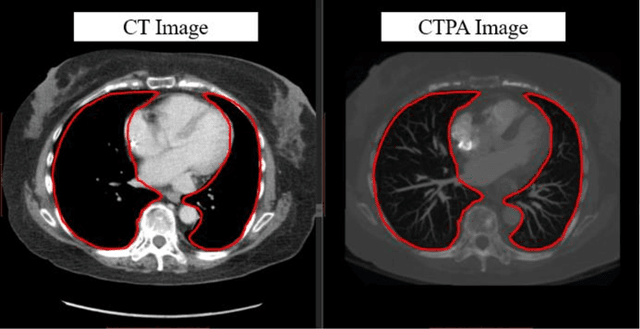

Abstract:The purpose of this research is to develop a system that generates simulated computed tomography pulmonary angiography (CTPA) images clinically for pulmonary embolism diagnoses. Nowadays, CTPA images are the gold standard computerized detection method to determine and identify the symptoms of pulmonary embolism (PE), although performing CTPA is harmful for patients and also expensive. Therefore, we aim to detect possible PE patients through CT images. The system will simulate CTPA images with deep learning models for the identification of PE patients' symptoms, providing physicians with another reference for determining PE patients. In this study, the simulated CTPA image generation system uses a generative antagonistic network to enhance the features of pulmonary vessels in the CT images to strengthen the reference value of the images and provide a basis for hospitals to judge PE patients. We used the CT images of 22 patients from National Cheng Kung University Hospital and the corresponding CTPA images as the training data for the task of simulating CTPA images and generated them using two sets of generative countermeasure networks. This study is expected to propose a new approach to the clinical diagnosis of pulmonary embolism, in which a deep learning network is used to assist in the complex screening process and to review the generated simulated CTPA images, allowing physicians to assess whether a patient needs to undergo detailed testing for CTPA, improving the speed of detection of pulmonary embolism and significantly reducing the number of undetected patients.